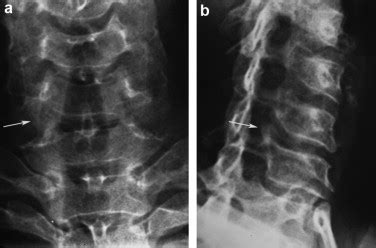

If you’re experiencing neck pain, stiffness, or any neurological symptoms that might suggest uncodiscarthrose, you’ll need to see a doctor for a proper diagnosis. Here’s what to expect during the diagnostic process. It all starts with a physical exam. Your doctor will ask about your symptoms and medical history. They will perform a physical exam to assess your range of motion, check for any tenderness in your neck, and evaluate your reflexes, muscle strength, and sensation in your arms and hands. This will help them to understand the nature and severity of your condition. To confirm the diagnosis and determine the extent of the damage, your doctor will likely order some imaging tests. X-rays can reveal the presence of bone spurs and any narrowing of the disc spaces . They’re a good first step to getting a clear picture of the bone structure. Further examination is possible with MRI (Magnetic Resonance Imaging) or CT scans (Computed Tomography) , which can provide more detailed images of the soft tissues, including the discs, nerves, and spinal cord. MRI is usually the preferred method because it offers the most comprehensive view. CT scans are an option, especially if you can’t have an MRI. Sometimes, additional tests, such as nerve conduction studies (NCS) and electromyography (EMG) , might be necessary to assess nerve function and pinpoint the location and severity of nerve compression. These tests measure the electrical activity in your nerves and muscles. In many cases, it’s a combination of these tests that allows doctors to get a precise diagnosis. Make sure to be open and honest with your doctor about your symptoms. It will help them get a clear idea of what’s going on.

Interpreting imaging results can be a bit tricky, but here’s a quick guide. X-rays will show any bone spurs or narrowed disc spaces , which are signs of osteoarthritis. The doctor looks for any changes in the bone structure that indicate wear and tear. MRI and CT scans provide more detailed views of the soft tissues. You’ll see the condition of the discs, any nerve compression, and the overall health of the spinal cord. The radiologist (the specialist who reads the scans) will look for: Discs that are bulging or herniated, which means they’re pressing on the nerves. Narrowing of the spinal canal (spinal stenosis), which compresses the spinal cord and nerve roots. Bone spurs (osteophytes) that are putting pressure on the nerves. The report will explain the findings, and your doctor will translate them into a diagnosis that you can understand. The images give the doctor a good idea of what’s going on, and the report will outline the specific issues, helping your doctor create a plan. Always remember to ask your doctor to explain the results in a way that you can easily understand, so you know exactly what is happening in your body. Don’t hesitate to ask questions; it’s your health, after all!